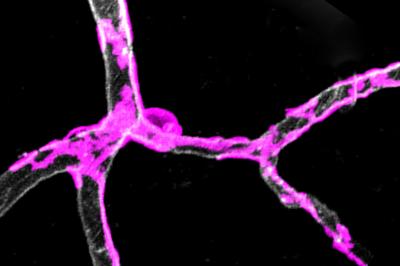

I periciti, le cellule-guardiane, sono avvolte intorno ai capillari nella corteccia cerebrale di un topo. Fonte: USCUn'anormalità in cellule particolari che avvolgono i vasi sanguigni nel cervello porta ad un deterioramento dei neuroni, con possibili influenze sullo sviluppo dell'Alzheimer, secondo uno studio guidato dalla University of Southern California.

Le 'cellule-guardiane' chiamate periciti circondano i vasi sanguigni; si contraggono e si dilatano per controllare il flusso di sangue verso parti attive del cervello.